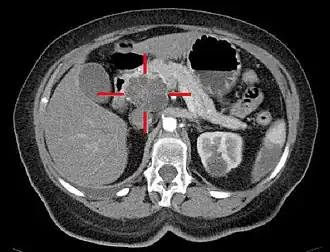

TAC com coloração artificial e elevado nível de contraste. A cruz delimita um adenocarcinoma macrocístico na cabeça do pâncreas.